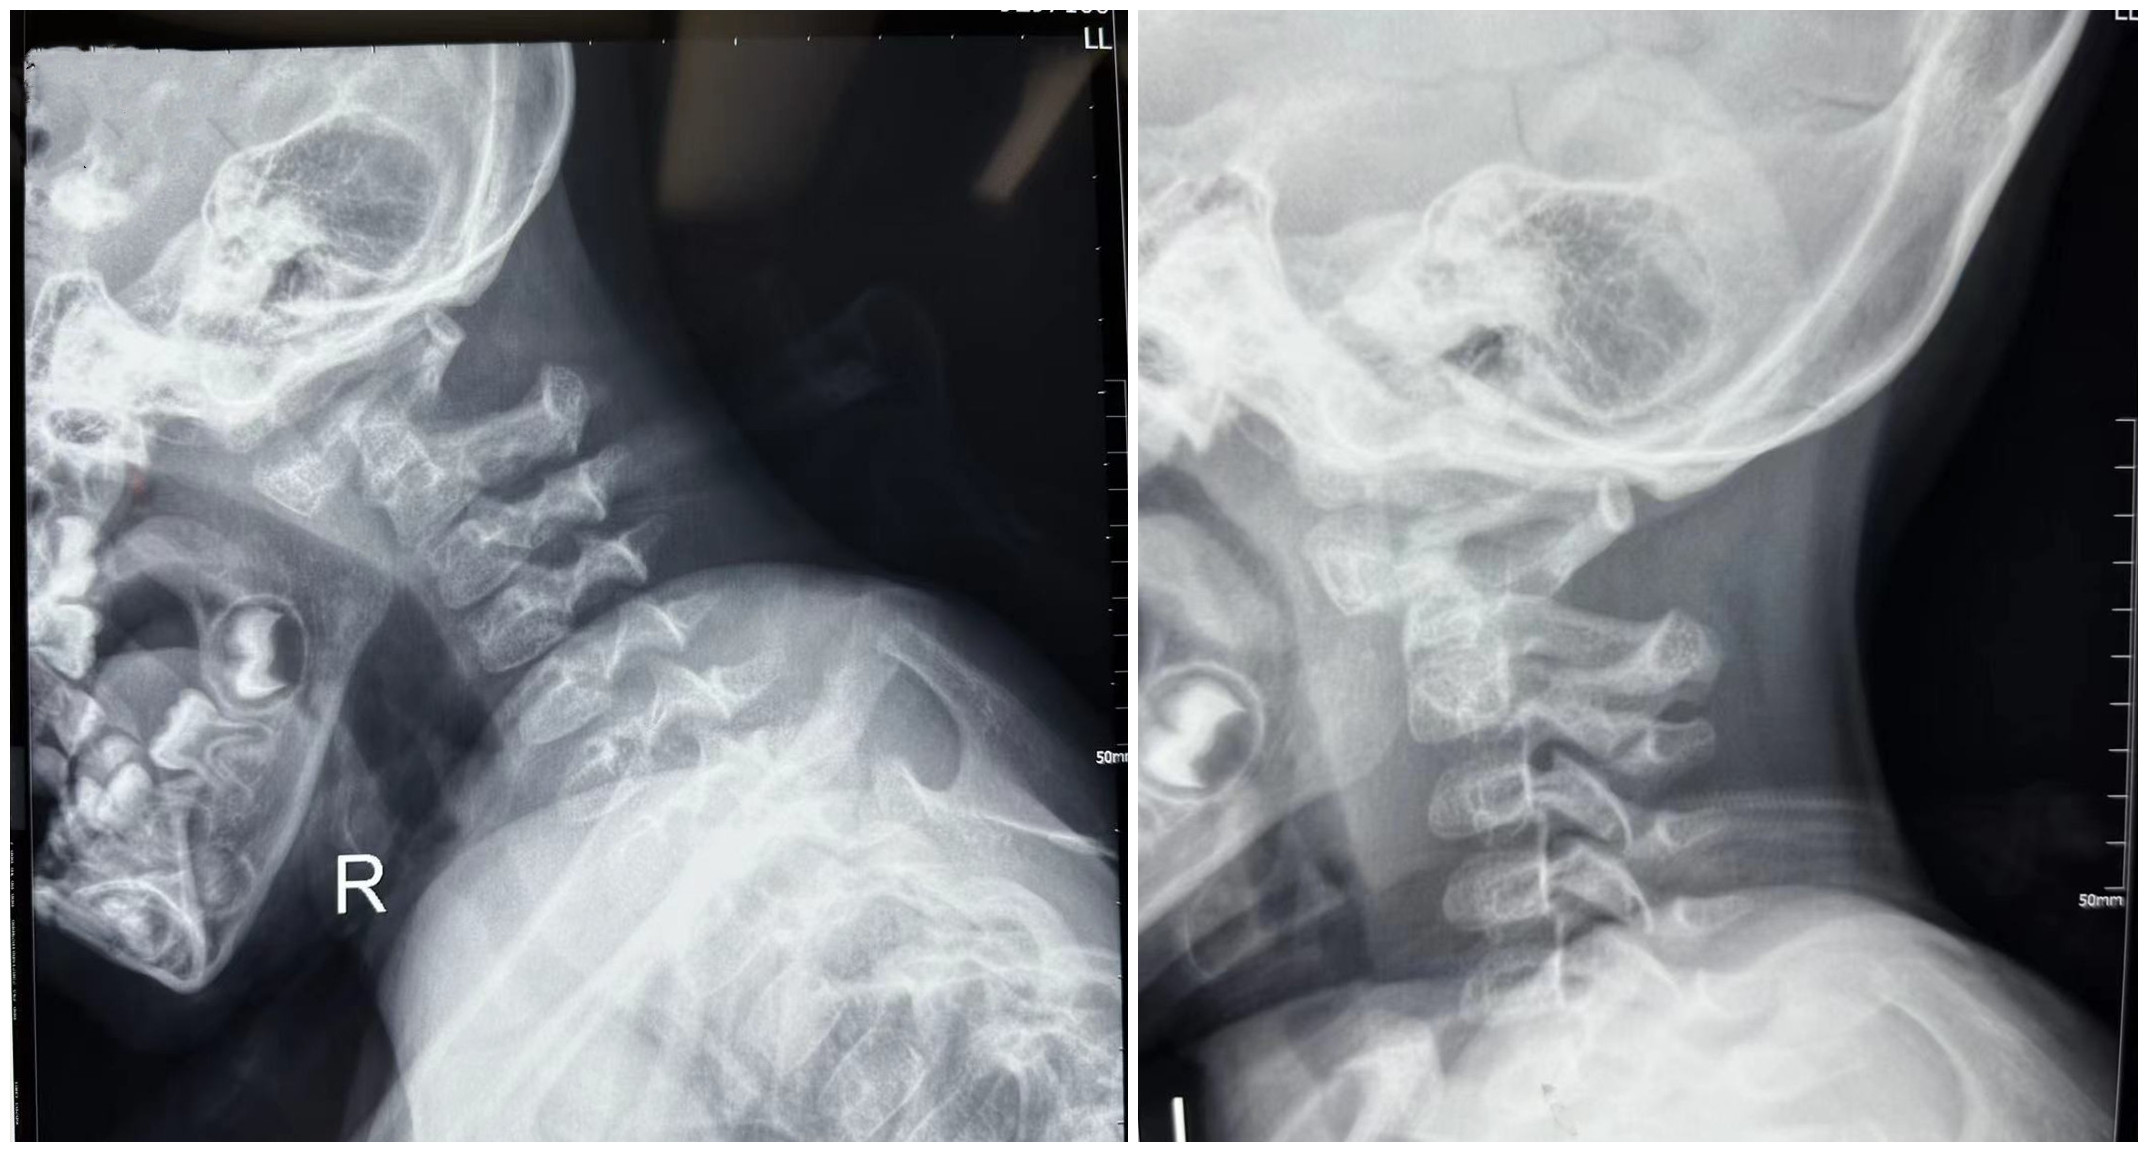

患儿术前影像学资料

患儿因车祸导致颈部疼痛、活动时疼痛明显加重,收住骨科二病区,主诊医生根据病史情况,结合检查、检验结果及临床表现诊断为寰枢椎脱位。因患儿年幼寰枢椎钉道狭窄,周围有重要的血管、神经,常规手术方式风险较大,经讨论评估后,拟使用“O”型臂导航系统辅助进行寰枢椎脱位手术。术中患儿病情稳定,术后症状明显改善,恢复良好。